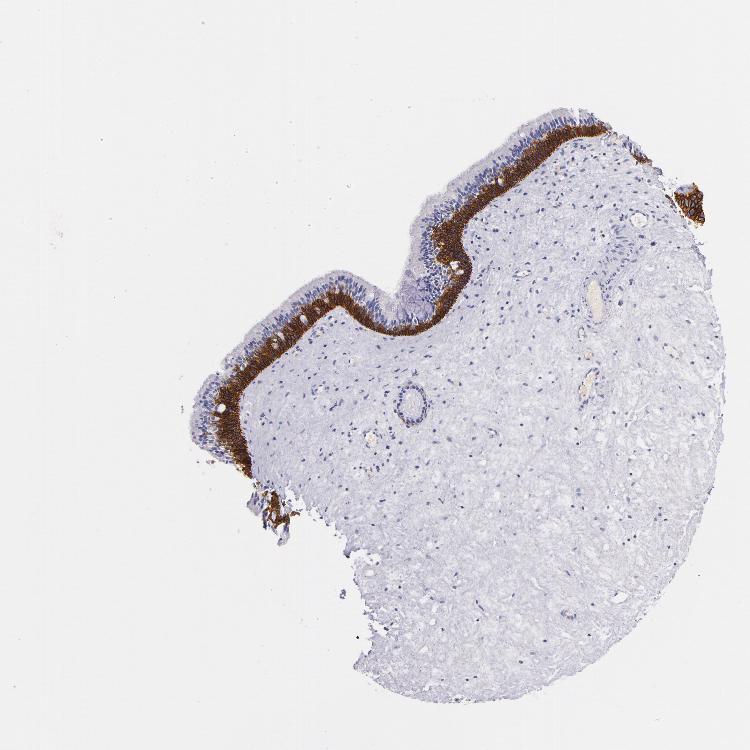

TISSUE PRIMARY DATA NASOPHARYNX Show tissue menu

Nasopharynx

NASOPHARYNX - Antibody stainingi

Antibody staining in the annotated cell types in the current human tissue is reported as not detected, low, medium, or high, based on conventional immunohistochemistry profiling in selected tissues. This score is based on the combination of the staining intensity and fraction of stained cells.

Each image is clickable and will lead to virtual microscopy that enables deeper exploration of all samples and also displays staining intensity scores, fraction scores and subcellular localization as well as patient and tissue information for each sample.

Antibody HPA005785Antibody CAB000112Antibody CAB000316

Basal cells High--

Ciliated cells (cell body) Medium--

Ciliated cells (cilia axoneme) Not detected--

Ciliated cells (ciliary rootlets) Not detected--

Ciliated cells (tip of cilia) Not detected--

Goblet cells Not detected--

Respiratory epithelial cells -HighHigh